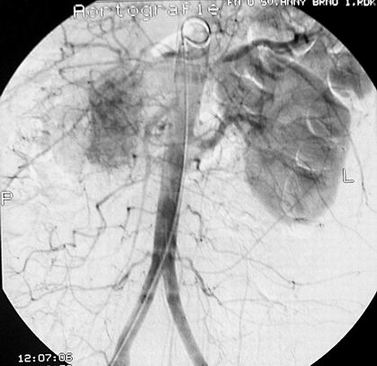

Obr. 2 Břišní AG – recidiva v lůžku po nefrektomii a postižení solitární ledviny

Jedná se o 59 letou pacientku. V září 1994 jí byla provedena nefrektomie pro nádor (tumorózní ložisko o průměru 8 cm, histologicky adenokarcinom ledviny s nekrózami a invazí do cév). Na doporučení onkologa podstoupila adjuvantní imunoterapii interferonem alfa. V dalších letech byla nemocná standardním způsobem sledována. Pravidelné kontroly (ultrazvukové vyšetření břicha, scintigrafie skeletu, rtg srdce a plic a CT retroperitonea) nenasvědčovaly o progresi choroby. V červnu 2001 byl ultrazvukem v lůžku po nefrektomii nalezen solidní útvar velikosti 46x39x33 mm, druhé suspektní ložisko se objevilo v kompenzatorně zvětšené levé ledvině. Předoperační diagnózu lokální recidivy a nádorového postižení solitární ledviny jsme potvrdili na CT a angiografickém vyšetření. Zvyklým způsobem jsme vyloučili generalizaci onemocnění. Pacientka byla připravena k operačnímu řešení. V říjnu 2001 jsme revidovali retroperitoneum vpravo. Ve výši pahýlu renální vény retrokaválně jsme nalezli oválný tumor velikosti asi 9x6x6 cm odtlačující dolní dutou žílu mediálně. Útvar se nám podařilo vcelku odstranit. Histologicky byla prokázána recidiva karcinomu z jasných buněk tvořící opouzdřený infiltrát solidně alveolárně uspořádaný, místy prokrvácený. V témže měsíci jsme operovali solitární ledvinu. Provedli jsme resekční záchovný výkon. Resekční linie byly bez nádorové infiltrace. Podle histologického nálezu se jednalo o dobře diferencovaný adenokarcinom ledviny. Po operacích pacientka podstoupila imunochemoterapii podle Atzpodiena na onkologickém oddělení. Kontrolní vyšetření neprokazují progeresi onemocnění. Biochemicky má normální renální funkce.